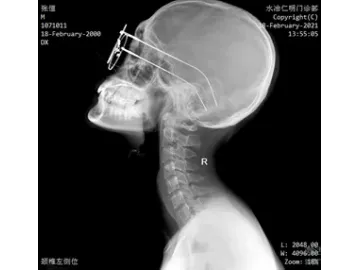

El modelo SHO-CMX01 es un sistema de rayos X fijado al techo pensado para quienes buscan precisión, rapidez y calidad en sus exámenes de imagen. Ideal para estudios de tórax, columna, abdomen y extremidades, se adapta perfectamente a centros médicos, departamentos de radiología, unidades de ortopedia y diagnóstico, entre otros. Este dispositivo médico no solo cubre radiografías convencionales, sino que también está preparado para procedimientos más exigentes como uniones de imágenes, visualización detallada de fracturas o estudios integrales en reconocimientos médicos. Es una solución integral que responde a las demandas clínicas más exigentes.Está equipado con un generador de 65.5 kW, un tubo de rayos X Canon de muy buen rendimiento, y dos detectores de panel plano (uno con cable y otro inalámbrico) que garantizan imágenes nítidas. Además, su colimador motorizado le permite ajustar el campo de exposición de forma rápida y precisa, optimizando cada procedimiento.

- Tubo de rayos X Canon de alta velocidad.

- Ideal para exposiciones prolongadas y de alta intensidad.

- Alta velocidad de rotación para una rápida disipación del calor y una mayor vida útil.

- Tiene una frecuencia de inversor ultraalta de 500 kHz y una corriente de tubo de hasta 800 mA, este sistema asegura una emisión de rayos X estable, con excelente calidad y resultados de imagen.

- Gracias a su generador de alto voltaje y gran potencia, se garantiza una radiación constante y precisa, ideal para diagnósticos confiables.

- Este sistema integra dos detectores planos (FPD), compatibles tanto con conexión por cable como inalámbrica, para adaptarse a distintas necesidades clínicas.

- Gracias a su formato de 17" x 17", ofrece un campo de visión amplio que evita tener que mover el detector durante el examen, facilitando así una visualización continua y sin interrupciones.

- Su tecnología de vanguardia garantiza imágenes nítidas, sin distorsiones y con una resolución excepcional, lo que mejora notablemente la precisión diagnóstica.

- Permite capturar imágenes puntuales en milisegundos durante la visualización o reproducción de los estudios. Esto brinda a los profesionales la posibilidad de detectar áreas sospechosas con mayor certeza, reducir errores de diagnóstico y acelerar la elaboración de informes.